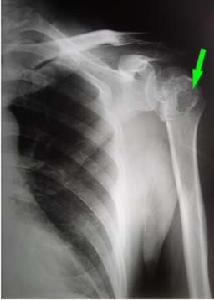

早期,滑膜紅腫滲出大量液體,關節囊、腱和腱鞘炎改變,關節明顯腫脹。滑膜炎繼續進行,富有血管的肉芽組織從關節軟骨邊緣的滑膜,向軟骨面伸展,最後可將軟骨完全覆蓋,遮斷了軟骨從滑液攝取營養,軟骨發生潰瘍。最後軟骨表面的肉芽組織纖維化,使上下關節面互相融合,形成纖維性關節強硬。關節附近的骨骼呈脫鈣和骨質疏鬆,肌肉和皮膚都萎縮。關節本身畸形或脫位。

(十一)手術治療 急性關節炎嚴重疼痛,局部有滲液時可抽降滲液,並注入類固醇抗炎藥,再使用夾板固定關節。腕及足下垂時可夾板固定及理療。持續性滑膜炎可考慮行滑膜切除術。肌腱破裂及神經受壓迫者應考慮手術治療。後期關節畸形及嚴重障礙者也可手術治療,如關節成形術、關節固定術、截骨術、人工關節置換術及伸側肌腱重建術等。